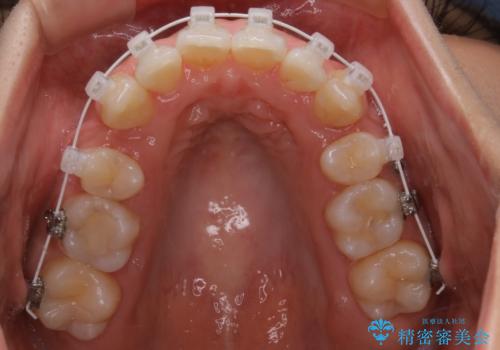

- ワイヤー矯正

左側のかみ合わせは、歯1本分かみ合わせが前にずれていました。上顎左右の奥歯を2本抜歯しています。

下顎は、歯の側面を少し削ることで歯並びを整えました。

上顎と下顎の奥歯の抜歯(計4本)を行う治療方法もありますが、口元のバランスのことも考え、上顎の抜歯のみで、治療を行いました。